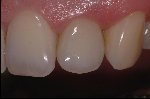

- Vollkeramische Restauration auf vollkeramischen Abutment

- Vollkeramische Restauration auf Implantat